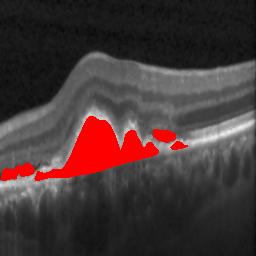

The qualitative results of the proposed system is shown in the Fig. 3. The detection task is evaluated using Area Under the Curve(AUC) metric and the segmentation task is evaluated using Dice Coefficient(DC) metric and the results are presented in Table1

| (a) De-noised OCT slice | (b)Predicted fluid region | (c)Manual fluid segmentation |

|

|

|

| (d) De-noised OCT slice | (e)Predicted fluid region | (f)Manual fluid segmentation |